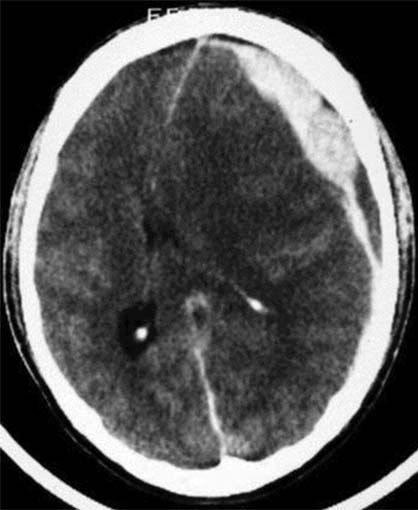

CCT nativ (ohne Kontrastmittel)

Zwischen Kalotte und Hirnoberfläche sichelförmige,

hyperdense (60-80HE) Raumforderung frontal links.

Starke Mittellinienverlagerung nach

rechts. Verstrichene

Gyri.

Akutes Subduralhämatom parietofrontal links.

Konsekutiv raumfordernde Wirkung des Subduralhämatoms links mit Verlagerung

der Mittellinie nach rechts.

Hirnödem.